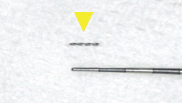

症例(マイクロスコープを用いた歯の根の治療:破折ファイルの除去)